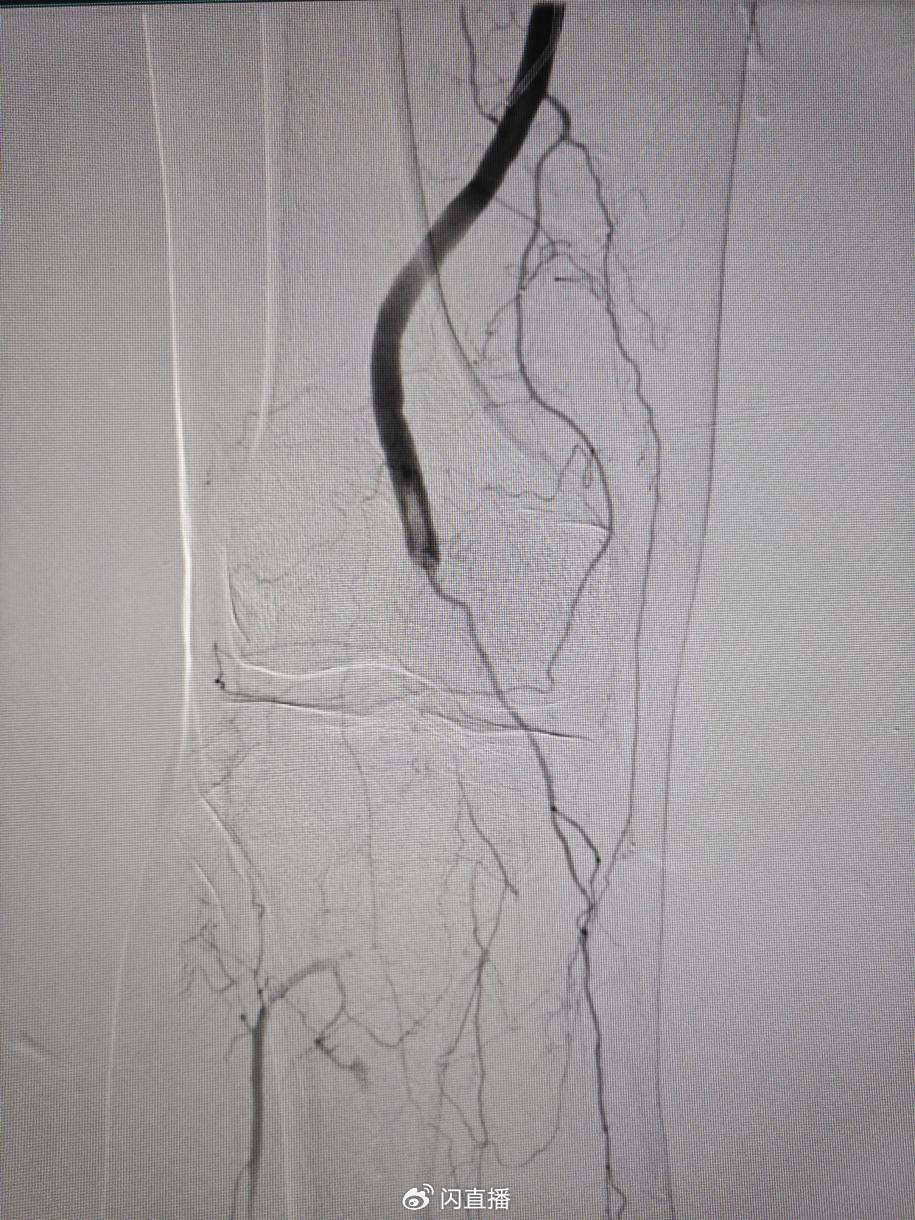

在与患者家属充分沟通后,吴智群主任率领李晨、陈健主治医师、田锦明住院医师在介入手术中心段永超主任团队积极配合下,给患者紧急进行动脉闭塞介入开通手术,术中发现腘动脉及以下血管完全闭塞,遂进行血管开通、血栓清除、PTA、置管溶栓治疗,患者术后即刻血流恢复,下肢皮色、皮温明显好转。

术后在护理团队的精心照护下,患者两天后再次造影:右下肢腘动脉及以下血管完全通畅,患者下肢皮温、皮色及动脉搏动恢复正常,疼痛完全消失,复查心肾功能好转,肌红蛋白降至330ng/ml。患者身体恢复,家属感动的泪流满面,感激西安市红会医院积极救治挽救老人的生命。